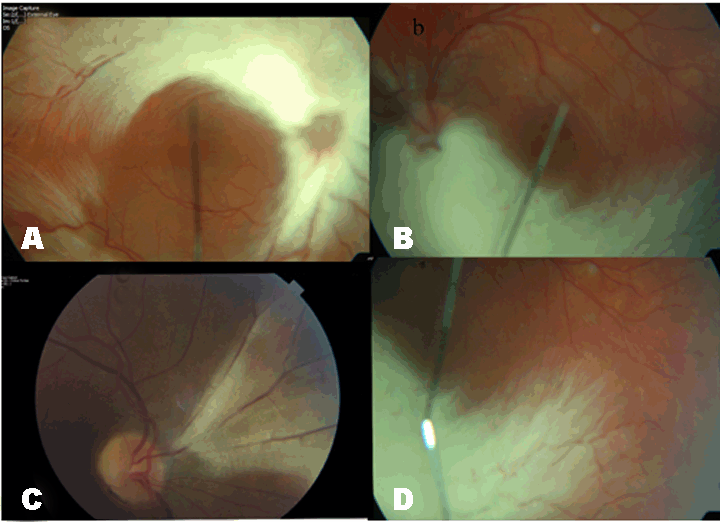

A three and half-year-old boy was referred because of reduced vision noticed during routine pre-school screening. He was otherwise well, but his uncle had tuberous sclerosis and grandmother retinitis pigmentosa. His unaided visual acuity was 6/60 in the right eye and 6/12 in the left and fundus examination revealed extensive myelinated nerve fibres along the superior and inferior arcades and involving the optic disc in the right eye and almost total myelination of the nerve fibres on the inferior half of the left eye. (Figure 1A-B) The anterior segment structures were normal in both eyes. He was refracted and the following prescription given; Right eye -3.0/+1.50 @ 90° and left eye -1.0/+2.75 @ 80°. An initial subnormal electroretinogram was found to be normal a year later and he has had no problems seeing at night or tuberous sclerosis features. However, the mother was also examined and found to have myelinated nerve fibres between 1.30 and 4 o'clock in right eye. (Figure 1C) The patient was kept on annual review but in December 2006, he complained of seeing white spots in his eyes. His corrected visual acuity was 6/24 in the right eye and 6/12 in the left and dilated fundoscopy revealed extensive vitreous condensation with bands and localized traction in the left eye. There was, however, no retinal tear. In July 2010, he developed vitreous hemorrhage in that left eye and examination confirmed localized proliferative vitreoretinopathy in the inferior-nasal quadrant. (Figure 1D) No active intervention has been initiated as there has since been slow regression of the abnormal vessels and clearing of the hemorrhage. | ||||||